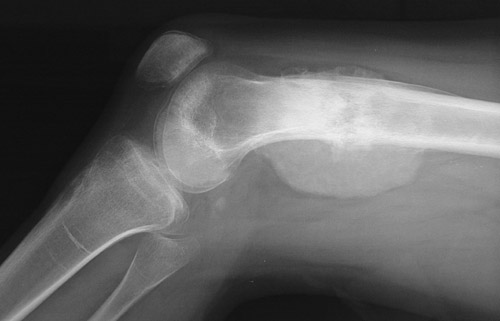

| In these lateral radiographs of the distal femur, an osteosarcoma involves the metaphyseal region. The tumor erodes and destroys the bone cortex, extending into soft tissue where irregular tumor bone with calcification is seen. There is extensive mass effect in the soft tissue adjacent to the bone. |